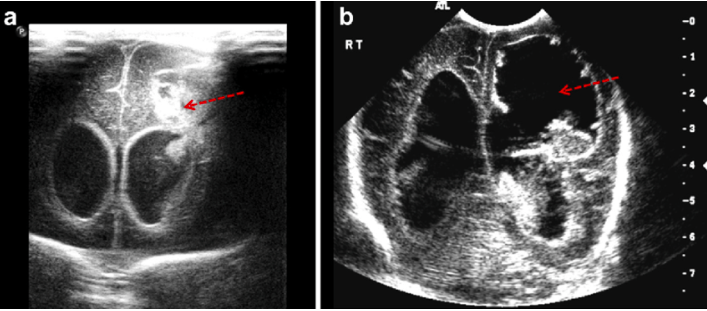

What does this ultrasound series show?

grade IV bleed (arrow in a), which developed into a porencephalic cyst (arrow in b).